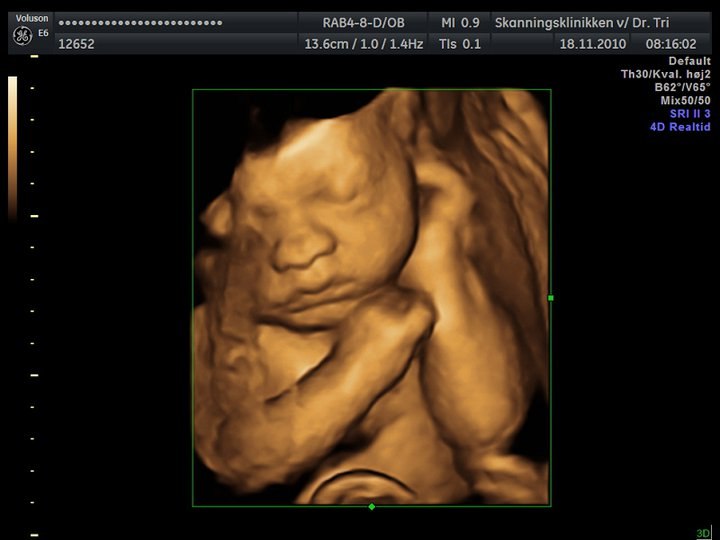

Så er det tid til nyt mavebillede - længe siden!! Tiden flyver bare afsted .. kun 2 mdr til termin  .. sidste torsdag var vi til 3d/4d scanning, så der kommer lige et billede med af den fine lillebror, som har sin søsters næse

Hvor er det et godt 3d-billede - det er da den lækreste lille bebs! Og også mor selvfølgelig

Det er et af de bedste 3d billeder jeg har set, man kan jo virkelig se alle hans træk, hvor er han sød.